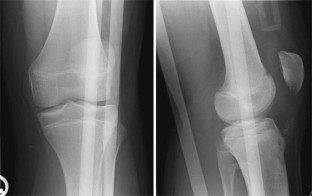

Abb. 1